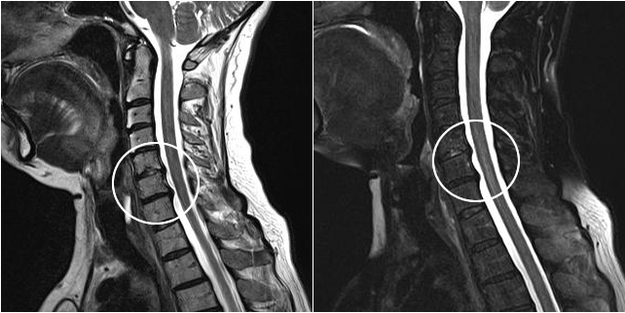

I moderni metodi diagnostici includono la risonanza magnetica e la TC, che consentono di esaminare con maggiore precisione i processi di distruzione della cartilagine e del tessuto osseo. Inoltre, utilizzando questa tecnica è conveniente diagnosticare ernie e altri difetti dei tessuti molli vicino alla fonte della malattia.

osteocondrosi cervicale sull'immagine MRI